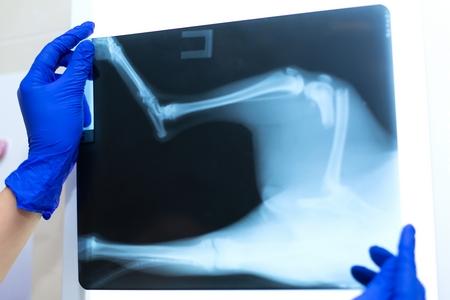

Mon chien doit faire une radiographie

Saviez-vous que la radiographie du chien est la technique d’imagerie médicale la plus pratiquée en médecine vétérinaire ? En effet, au cours de la vie de votre boule de poils, vous allez probablement devoir lui faire passer une radio. D’où l’intérêt de se familiariser avec cette méthode d’examen. Comment se déroule une radiographie ? Dans quel cas est-elle conseillée ? Et combien vous coûte-t-elle ? Mouss vous dit tout !